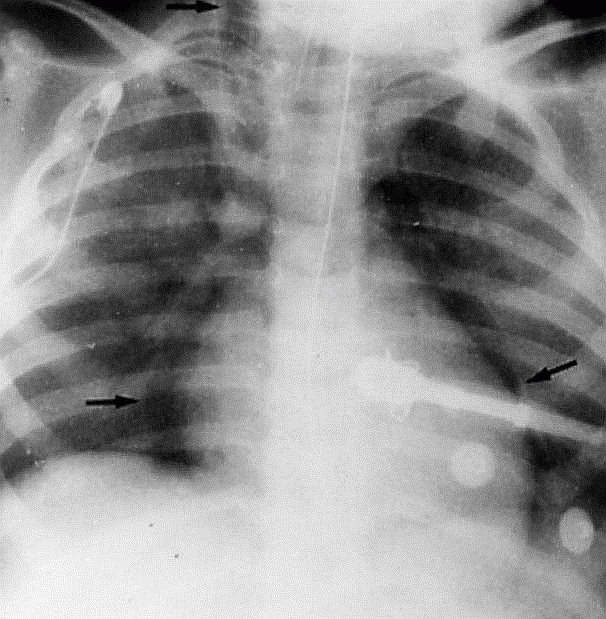

Sepsisli xəstələrdə rentgenoloji müayinədə mediastinumda hava görünməsi yüksək şübhə əlamətidir (Şəkil 9).

Şəkil 9. Mediastinal emfizema